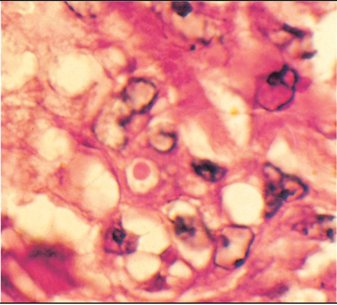

Examen anatomo-pathologique

A l'examen histologique, la présence de corps d'inclusion intranucléaires est caractéristique de l'herpèsvirose, contrairement au capripoxvirus de la DNC associé à des inclusions intracytoplasmiques (figures n° 6a et 6b). J.B.-P.